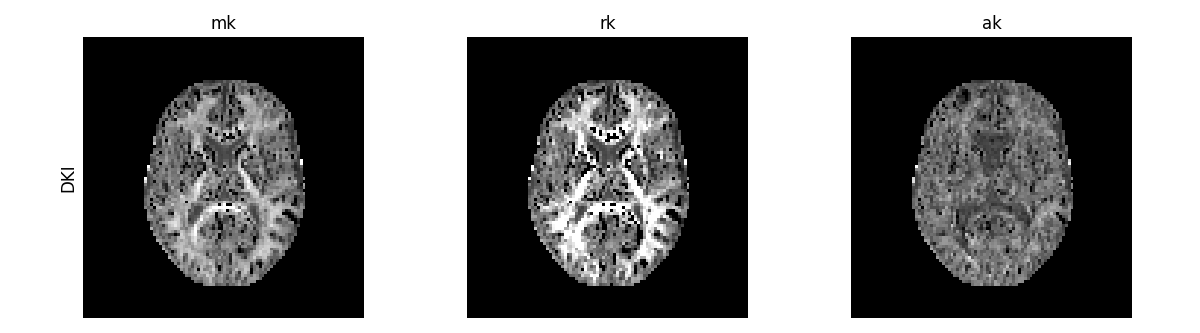

In addition to the standard diffusion statistics, the DiffusionKurtosisFit instance can be used to estimate the non-Gaussian measures of mean kurtosis (MK), the radial kurtosis (RK) and the axial kurtosis (AK).

maps = ["mk", "rk", "ak"]

compare_maps(

[dkifit],

maps,

fit_labels=["DKI"],

map_kwargs={"vmin": 0, "vmax": 1.5},

filename="DKI_standard_measures.png",

)

DKI standard kurtosis measures.

The non-Gaussian behaviour of the diffusion signal is expected to be higher when tissue water is confined by multiple compartments. MK is, therefore, higher in white matter since it is highly compartmentalized by myelin sheaths. These water diffusion compartmentalization is expected to be more pronounced perpendicularly to white matter fibers and thus the RK map presents higher amplitudes than the AK map.